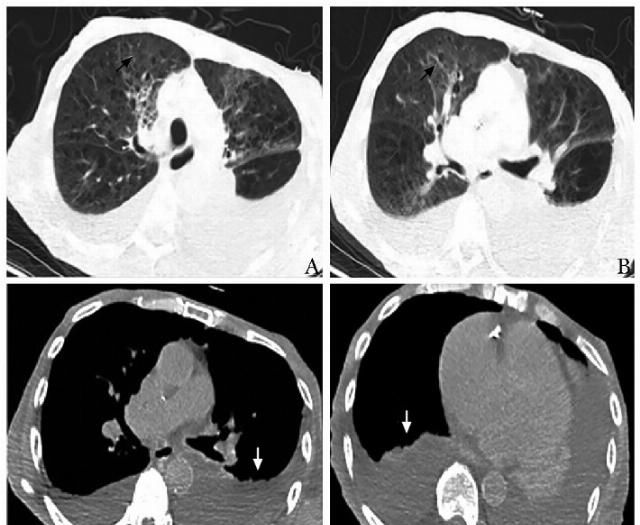

A、B.肺窗表现;C、D.纵隔窗表现

但新近出现低氧血症,复查胸部CT提示新见双肺弥漫性磨玻璃影、胸水增多,考虑继发卡氏肺孢子菌感染不能除外。同时,老年综合评估提示存在衰弱、肌少症,营养不良及波动性认知功能障碍,均预示预后不良。

HES常见肺部受累表现为嗜酸性粒细胞性肺炎,影像学可见游走性渗出影,实性或磨玻璃样病变,沿支气管或胸膜下分布,本质上为EOS肺泡腔内浸润所致。该患者无典型的HES肺浸润表现,主要表现为双上肺陈旧性肺结核钙化灶,全小叶性肺气肿,提示该患者呼吸储备功能差。

近期新出现低氧血症,对于高龄、免疫抑制状态的老年患者,需警惕合并机会性感染,结合双肺新发磨玻璃样渗出影的影像学表现,考虑卡氏肺孢子菌肺炎可能性大,总体预后很差。